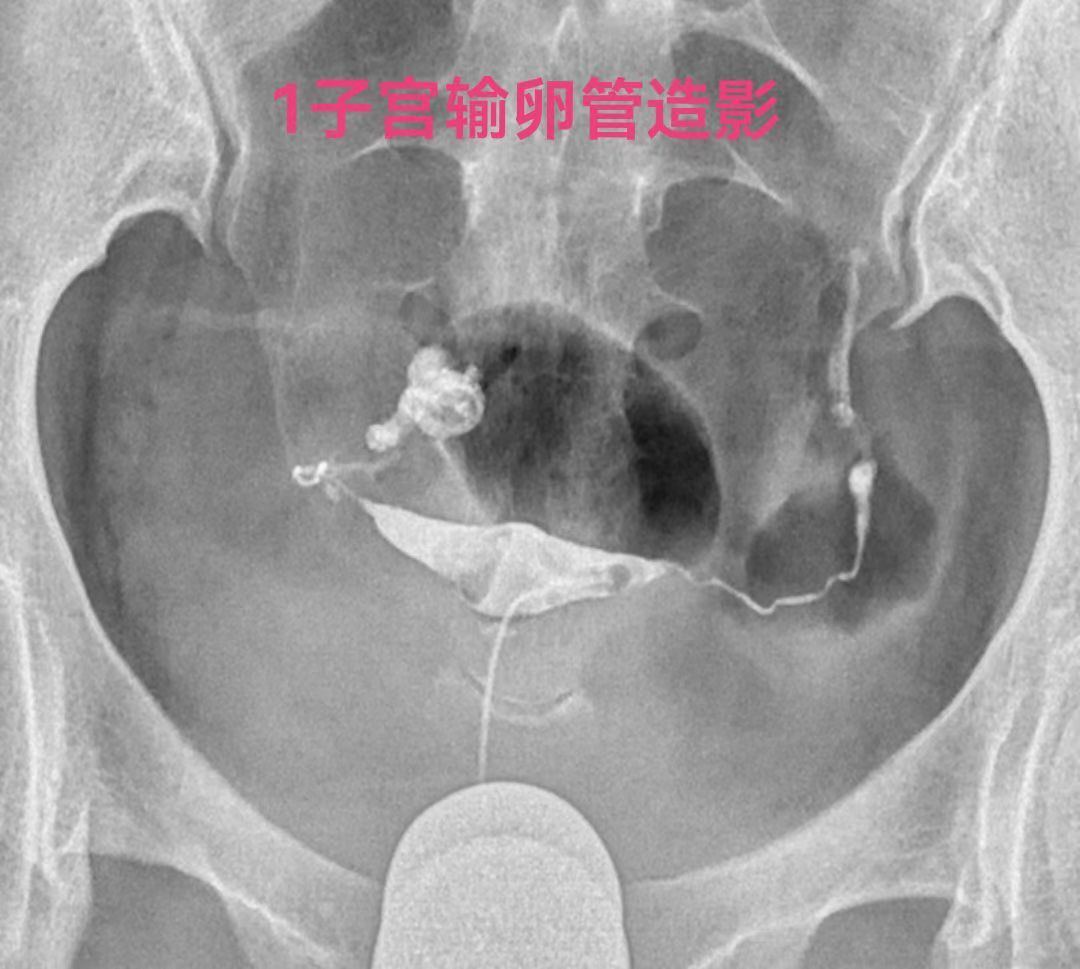

在试管婴儿前处理输卵管积水的方法主要有二种:一种是腹腔镜下输卵管近段结扎并积水远段造口术,另一种是在放射介入科做得近段介入栓塞术。输卵管积水近段介入栓塞术是对严重的盆腔粘连不能腹腔镜手术和开腹手术,或者不愿意腹腔镜手术和开腹手术者的一种最佳选择。输卵管积水近段介入栓塞术是在X 线监视下将微导管通过阴道-宫颈-子宫宫角进入输卵管的间质部将一个微弹簧圈送入输卵管间质部和峡部, 来阻断输卵管腔内的通路,使积水不能返流到子宫,不再影响胚胎的着床和发育,提高试管婴儿的成功率。

输卵管间质部长约1cm,管腔狭窄,直径0.5-1mm。峡部在间质部外侧,长约2-3cm,直径约0.2-2mm。输卵管间质部和峡部的管腔是输卵管最细的部位,是最适合的栓塞的部位,输卵管间质部和峡部的总长度也就3-4厘米。输卵管栓塞铂金弹簧圈最常用的是2-2(长2厘米,两端直径都是2毫米)或3-2(长2厘米,一端直径小2毫米另一端直径大是3毫米,就是向宝塔一样,有时被称为塔圈)。一般栓塞一枚弹簧圈可以完全栓塞间质部和峡部的输卵管管腔,而且一枚2厘米长的弹簧圈的两端由于弹性回缩力的回缩,像哑铃一样两端较粗大,可以卡在输卵管内壁上,完全封闭管腔,所以栓塞一枚弹簧圈栓塞最牢固。就像红酒瓶塞一个塞子的最紧实,只有栓塞位置不好才补栓多一个串联的弹簧圈。

因此致密栓塞不仅是多花钱多受罪,而且还没有栓塞一个合适的弹簧圈栓塞的严实。请看下图双侧输卵管积水两侧输卵管各栓塞一个弹簧圈的术前术后标识。